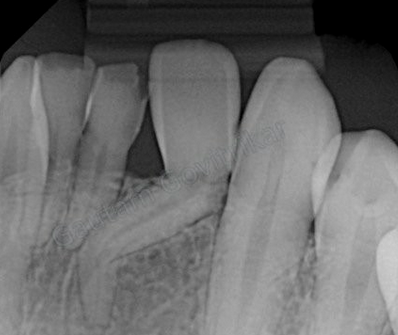

Dentinogenesis Imperfecta

(Mutation of the dentin sialophosphoprotein gene (DSPP). If occurs with osteogenesis imperfecta, it is termed osteogenesis imperfecta with opalescent teeth. Bulbous crowns, cervical constriction, thin roots, early obliteration of root canals)